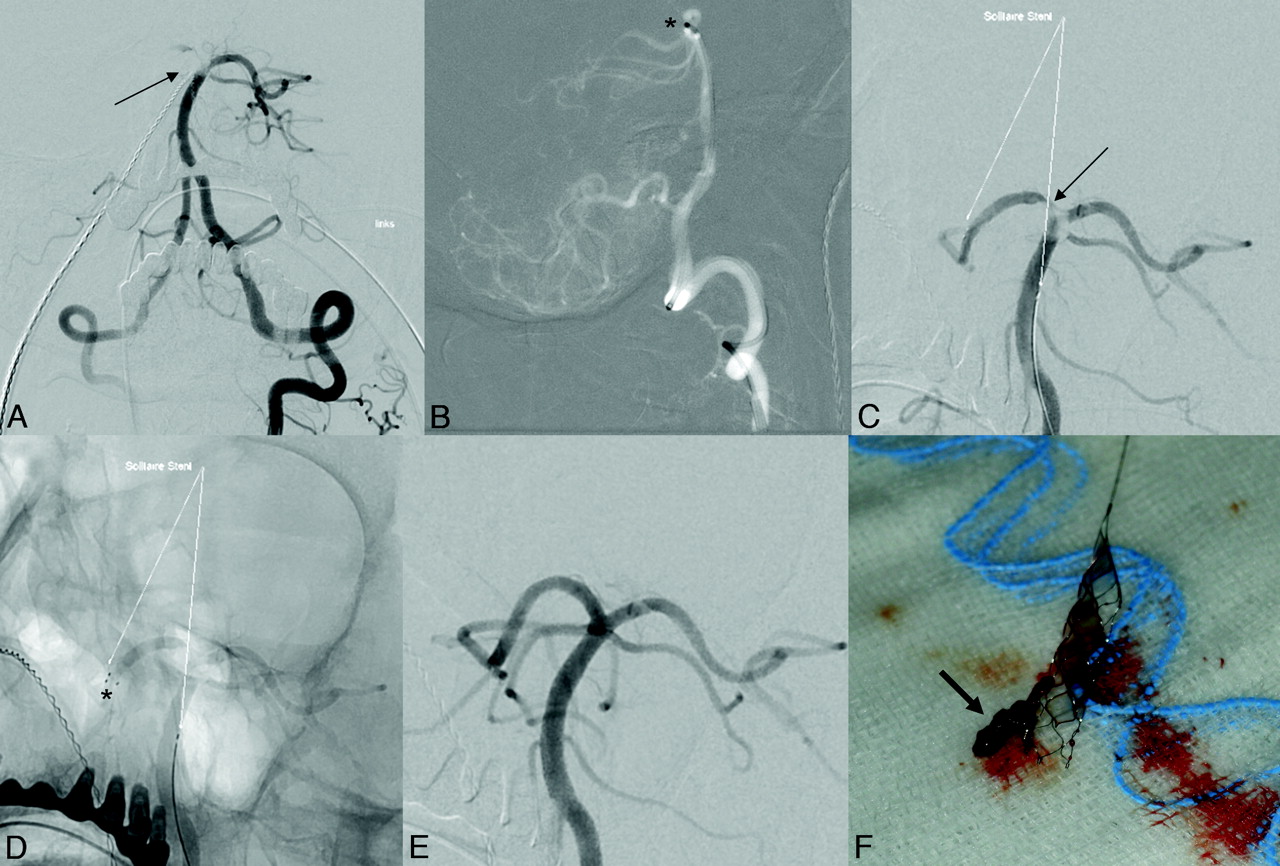

Delivery of the Solitaire FR Revascularization Device was technically feasible in all patients of group A. The retrievable stent was used as the exclusive endovascular treatment in 4 patients. Flow arrest was applied during stent retrieval in 12 patients. Only 1 retrieval attempt with the stent was performed in 13 patients. Two retrieval attempts were performed in 2 patients and 3 retrieval attempts in another 2 patients. Overall, 23 retrieval attempts were performed. Immediate recanalization after deployment of the Solitaire FR Revascularization Device was observed in 18/23 (78%) attempts (Fig 1). Retrieval of the stent resulted in sufficient recanalization in 14/17 patients (82%). In 12 patients (71%), thrombotic material was removed and normally found attached to the stent meshes (Fig 1). No thromboembolic occlusion of a previously unaffected artery was found at follow-up angiography after retrieval. In 2 of 3 patients with failed recanalization after removal of the Solitaire FR Revascularization Device, the vessel was finally recanalized by permanent placement of an intracranial stent (Wingspan). Overall, 35% of the patients in group A received intravenous thrombolysis, 53% intra-arterial thrombolysis, 41% thromboaspiration, and 24% an additional stent placement with or without PTA (2 stent placements into intracranial arteries and 2 stent placements into the proximal internal carotid artery). Eighty-eight percent of the interventions in group A were performed during general anesthesia. No symptomatic intracranial hemorrhages or device-related adverse events were encountered.

Occlusion of the tip of the basilar artery. Symptom onset >12 hours before angiography. NIHSS score 6. A, Antero-posterior view of left vertebrobasilar angiogram depicts thrombus in the distal basilar artery, residual flow to left posterior cerebral artery, occlusion of right posterior cerebral artery and right superior cerebellar artery. B, Thromboaspiration attempt–tip of Vasco35+ASPI (*) in the tip of basilar artery (lateral view). C, After unsuccessful thromboaspiration, deployment of a Solitaire FR 4/20. D, Distal stent markers in the right posterior cerebral artery. The proximal stent ends in the basilar artery. Note incomplete recanalization of the right posterior cerebral artery after stent placement. E, Complete recanalization after stent retrieval. F, Solitaire FR Device with captured thrombus (arrow). Time to recanalization 20 minutes.